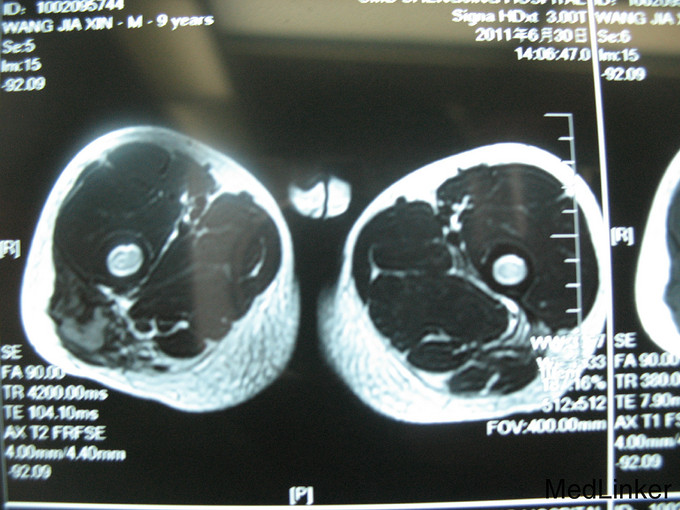

右臀部手术区可见15cm长的手术瘢痕,瘢痕下可 及硬韧肿物大小约10x7cm,边界不清,活动度差。

侵袭性纤维瘤病是一种不明原因、不发生转移的成纤维细胞性瘤样肿物。起源于肢体和韧带的肌筋膜结构,累及骨骼肌腱膜和筋膜,并对周围组织产生压迫。病变很易局部复发,并呈侵袭性生长,最常见于青年人的肩胛带、股部及臀部。侵袭性纤维瘤术后复发几率高,对周围组织侵袭性强。本例患者给予扩大切除术后随诊至今未发现复发病灶。